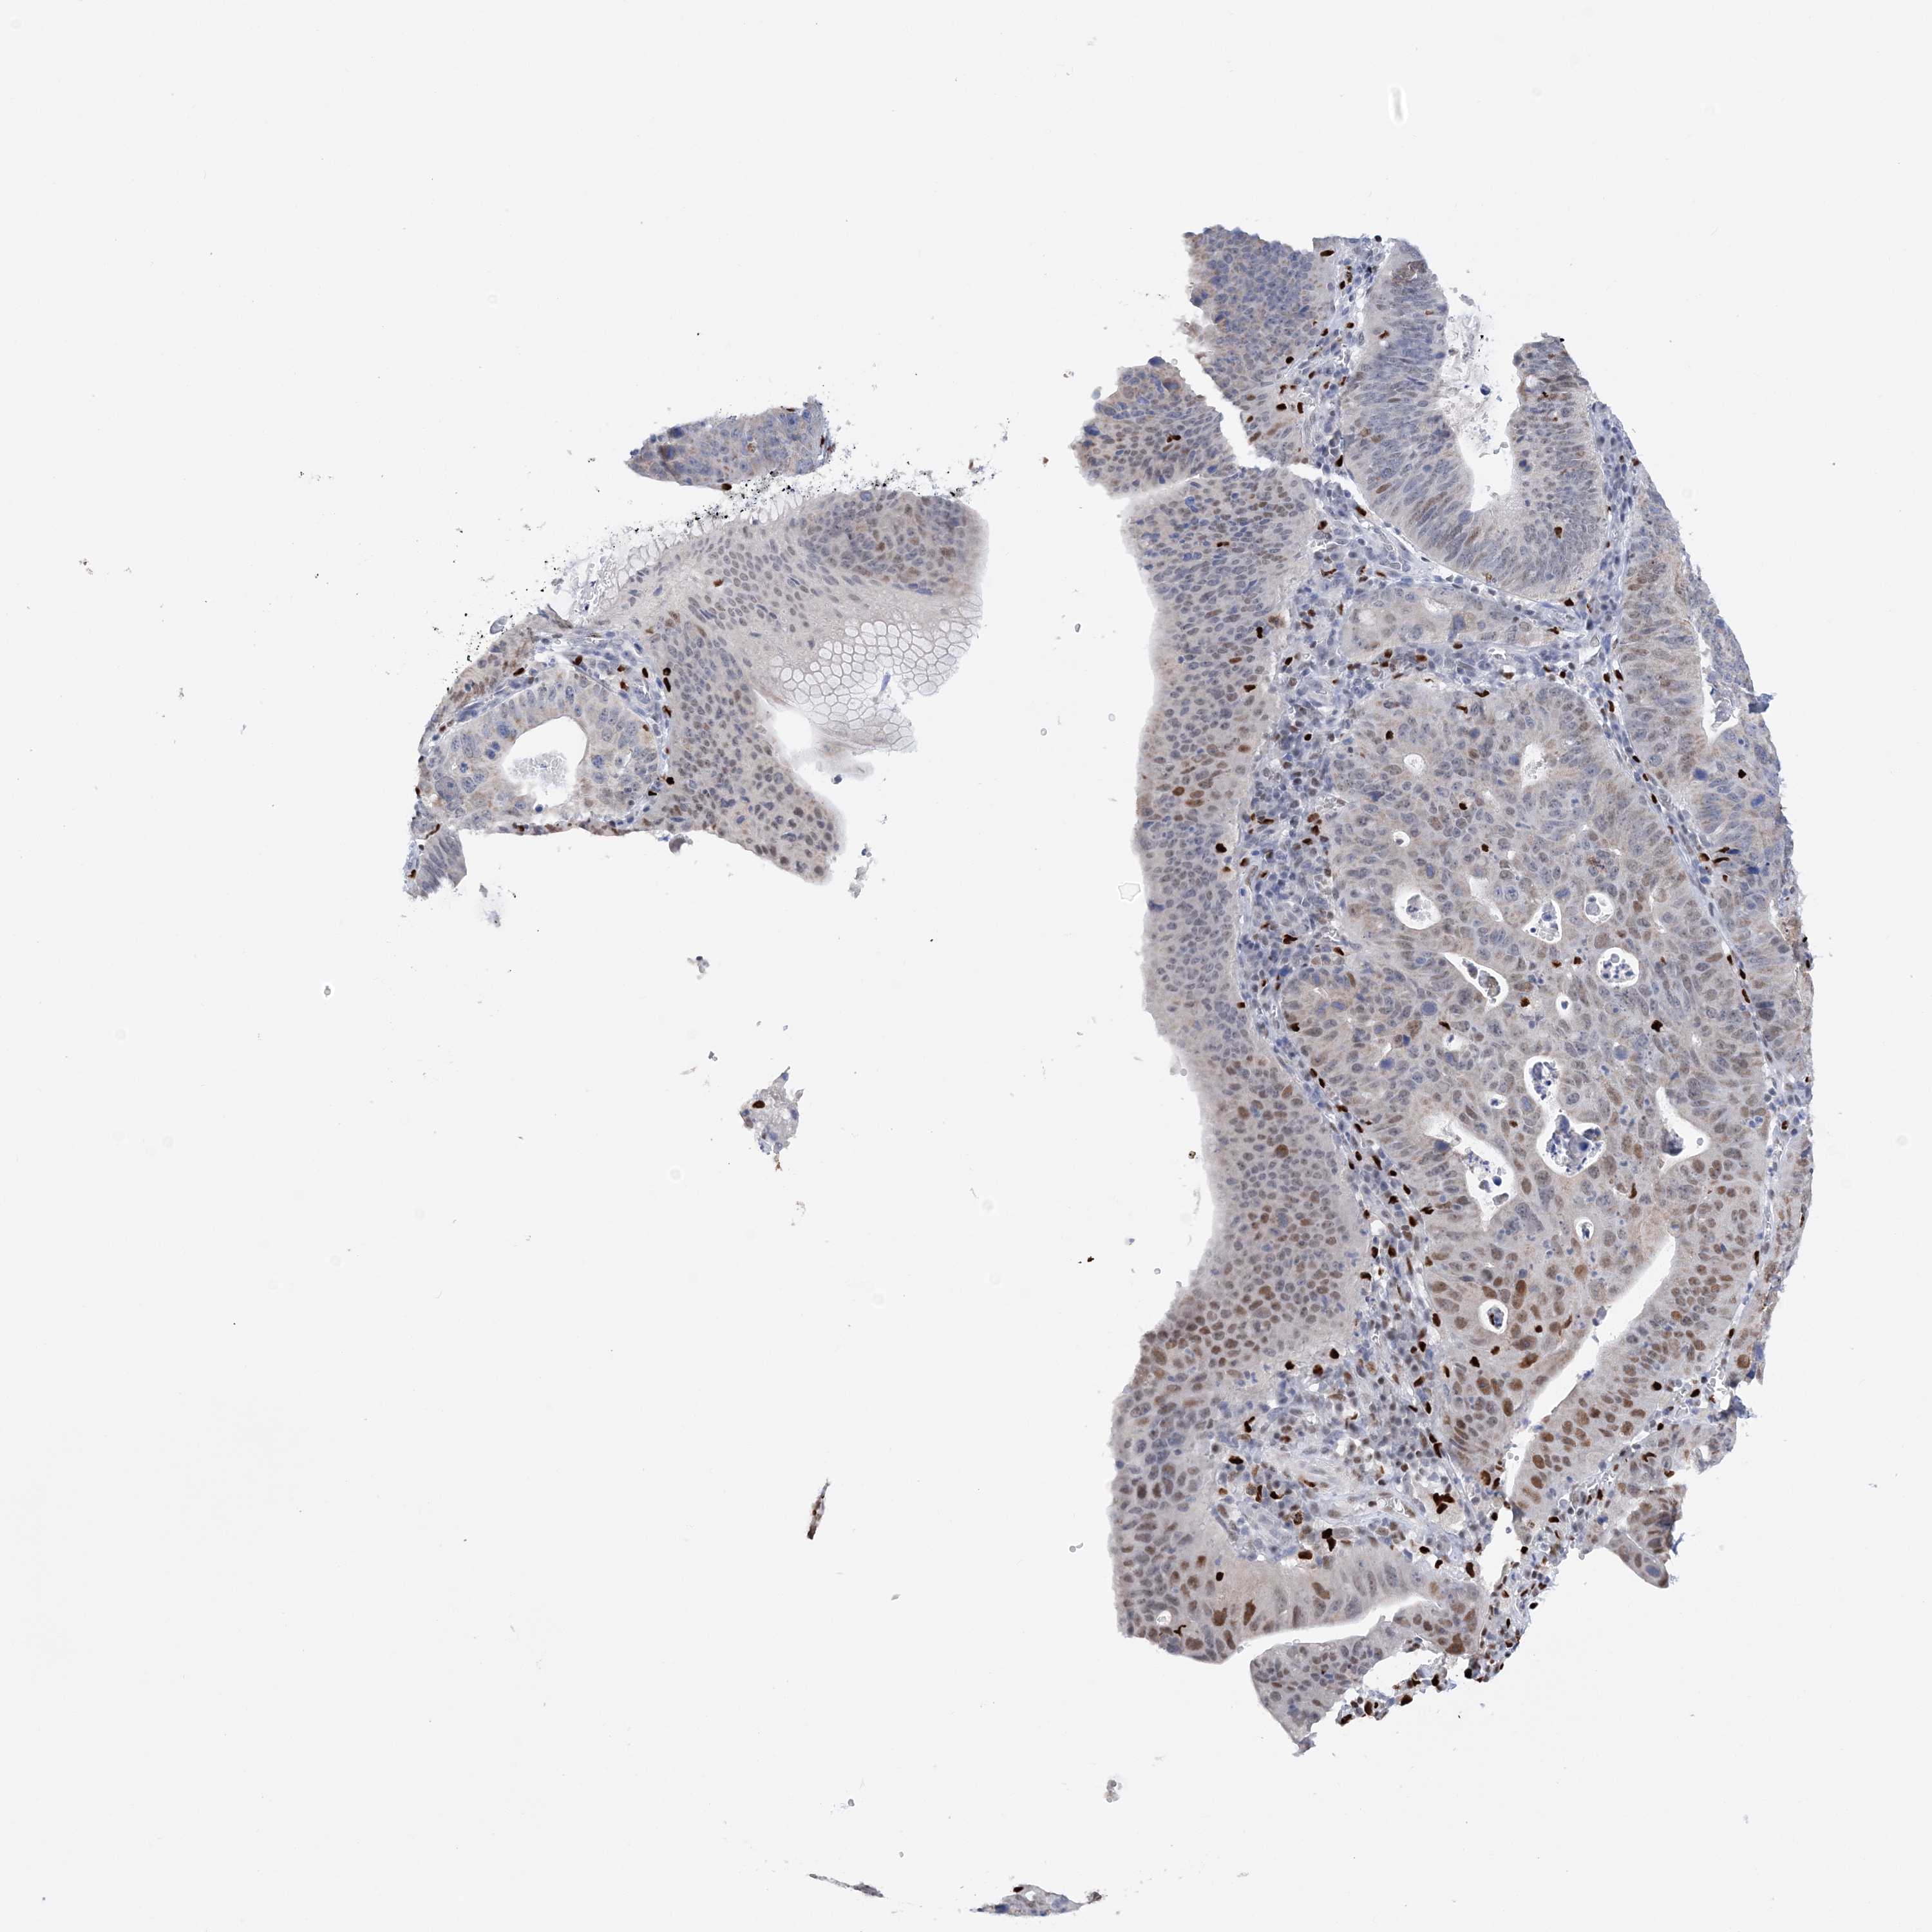

STOMACH CANCER - Protein expressioni

A mouse-over function shows sample information and annotation data. Click on an image to view it in a full screen mode. Samples can be filtered based on level of antibody staining by selecting one or several of the following categories: high, medium, low and not detected. The assay and annotation is described here.

Note that samples used for immunohistochemistry by the Human Protein Atlas do not correspond to samples in the TCGA dataset.

Antibody stainingi

Antibody staining in the annotated cell types in the current human tissue is reported as not detected, low, medium, or high, based on conventional immunohistochemistry profiling in selected tissues. This score is based on the combination of the staining intensity and fraction of stained cells.

Each image is clickable and will lead to virtual microscopy that enables deeper exploration of all samples and also displays staining intensity scores, fraction scores and subcellular localization as well as patient and tissue information for each sample.

Antibody HPA036999

Antibody HPA041289

Staining

High

Medium

Low

Not detected

Intensity

Strong

Moderate

Weak

Negative

Quantity

>75%

75%-25%

<25%

None

Location

Nuclear

Cytoplasmic/membranous

Cytoplasmic/membranous,nuclear

Adenocarcinoma, NOS

Adenocarcinoma, High grade